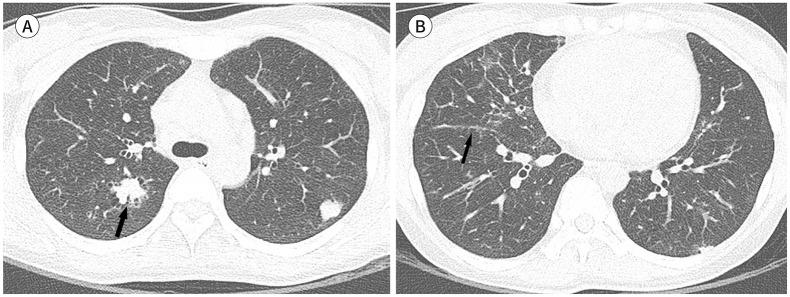

Immunoglobulin G4-related disease (IgG4-RD) is a chronic inflammatory condition involving multiple organs, including the salivary or lacrimal glands, orbit, pancreas, bile duct, liver, kidney, retroperitoneum, aorta, lung, and lymph nodes. It is histologically characterized by tissue infiltration with lymphocytes and IgG4-secreting plasma cells, storiform fibrosis, and obliterative phlebitis. In the thoracic involvement of IgG4-RD, mediastinal lymphadenopathy and perilymphangitic interstitial thickening of the lung are the most common findings. Peribronchovascular and septal thickening and paravertebral band-like soft tissue are characteristic findings of IgG4-RD. Other findings include pulmonary nodules or masses, ground-glass opacity, alveolar interstitial thickening, pleural effusion or thickening, mass in the chest wall or mediastinum, and arteritis involving the aorta and coronary artery. Radiologic differential diagnosis of various malignancies, infections, and inflammatory conditions is needed. In this review, we describe the imaging findings of IgG4-RD and the radiologic differential diagnoses in the thorax.

免疫球蛋白G4相关性疾病(IgG4-RD)是一种累及多个器官的慢性炎症性疾病,这些器官包括唾液腺或泪腺、眼眶、胰腺、胆管、肝脏、肾脏、腹膜后、主动脉、肺和淋巴结。其组织学特征为淋巴细胞和分泌IgG4的浆细胞浸润组织、席纹状纤维化和闭塞性静脉炎。在IgG4-RD累及胸部时,纵隔淋巴结肿大和肺淋巴管周围间质增厚是最常见的表现。支气管血管周围和小叶间隔增厚以及椎旁带状软组织是IgG4-RD的特征性表现。其他表现包括肺结节或肿块、磨玻璃影、肺泡间质增厚、胸腔积液或增厚、胸壁或纵隔肿块以及累及主动脉和冠状动脉的动脉炎。需要对各种恶性肿瘤、感染和炎症性疾病进行影像学鉴别诊断。在本综述中,我们描述了IgG4-RD的影像学表现以及胸部的影像学鉴别诊断。